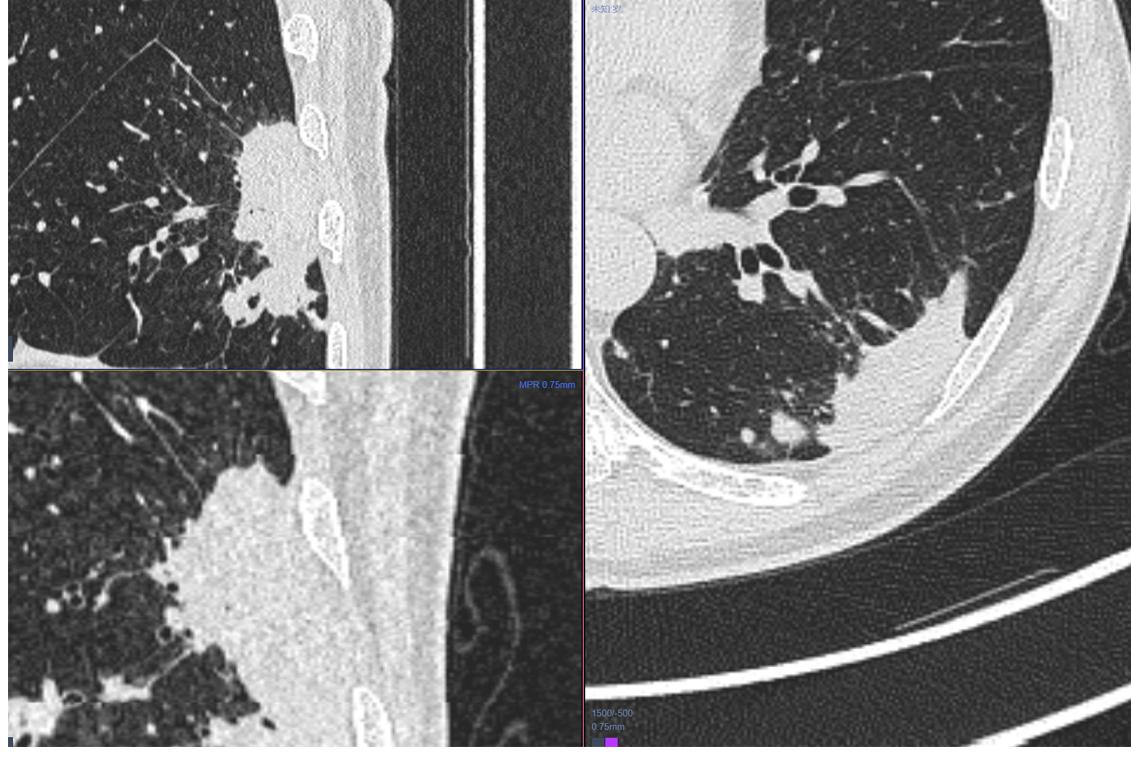

4.男性 53岁 以脑梗塞灶入院,发现内内3cm大软组织肿块。

没有什么能够阻挡我对这个病灶的诊断,考虑为肉芽肿性病变。